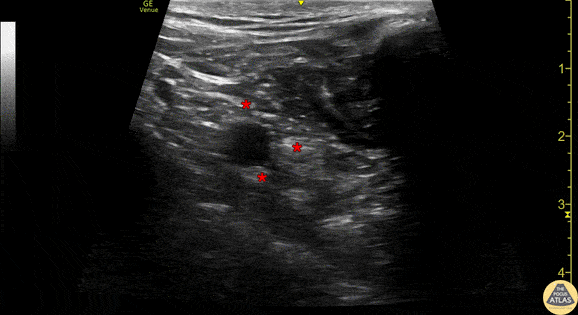

Demonstration of the anatomy of the infraclavicular brachial plexus with the linear transducer in a parasagittal orientation just lateral to the mid-clavicular line. The pulsating subclavian artery can be seen surrounded by the brachial plexus (*). The hyperechoic clavicle is seen in short axis at the right of the image. Sliding pleura can be seen deep to the artery/brachial plexus. Drs. Sam Paskin-Flerlage, PGY4 and Michael Heffler, PGY3 Denver Health Residency in Emergency Medicine